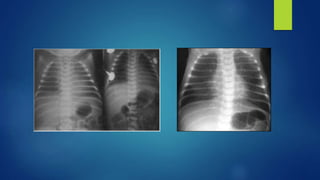

Hallazgos radiográficos

A. Hallazgos radiográficos, en infantes con SAM

incluyen:

 Infiltrados difusos.

 Consolidación

 Atelectasia

 Derrame pleural

 Espacios aéreos (neumotórax, neumomediastino)

 Pulmón húmedo, similar a lo hallazgos vistos en la T.T. RN.

 Hipovascularidad

 Aparentemente limpio, apariencia virtualmente normal.

Atelectasia

Neumomediastino